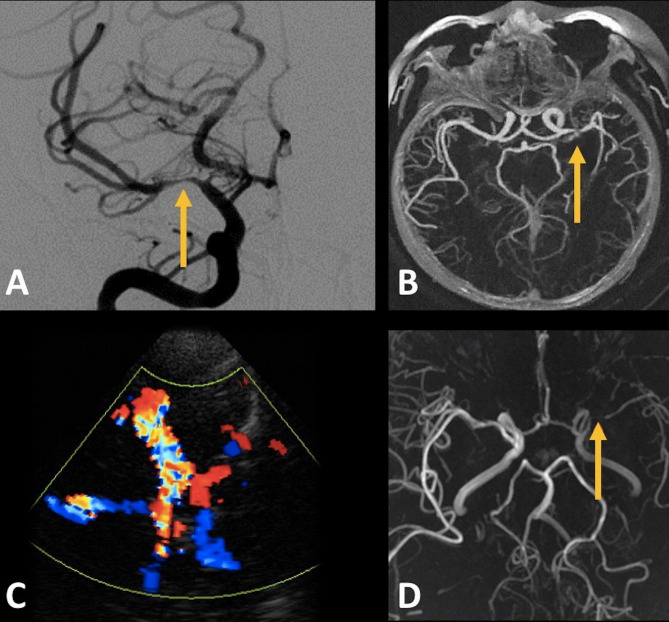

Main body: Atherosclerotic plaque accumulation and progressive arterial stenosis of major intracranial arteries comprise the pathophysiological hallmark of ICAD. In clinical practice, the diagnosis of intracranial artery stenosis (ICAS) or high-grade ICAS is reached when luminal narrowing exceeds 50% and 70%, respectively. Advanced neuroimaging, including high-resolution vessel wall MRI (HRVW-MRI), has recently enabled ICAD detection before luminal stenosis occurs. While earlier studies disclosed significant racial disparities in ICAS prevalence, with higher rates among Asians, Hispanics, and Blacks, recent evidence reveals rising detection rates of ICAD among White populations. Genetic, environmental and epigenetic factors have been suggested to confer an increased susceptibility of certain ethnicities and races to ICAD. Nevertheless, with improved accessibility to advanced neuroimaging, ICAD is increasingly recognized as an underlying stroke etiology among White patients presenting with acute ischemic stroke and stroke of undetermined etiology. While conventional management of ICAS entails risk factor modification, pharmacotherapy, and endovascular treatment in selected high-risk patients, substantial progress remains to be made in the management of ICAD at its early, pre-stenotic stages.